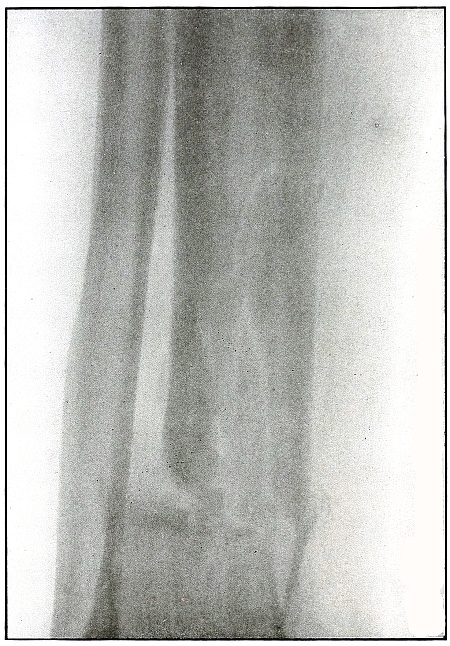

Gunshot fracture, tibia and fibula |

130 |

| 61. |

Gunshot fracture, tibia and fibula |